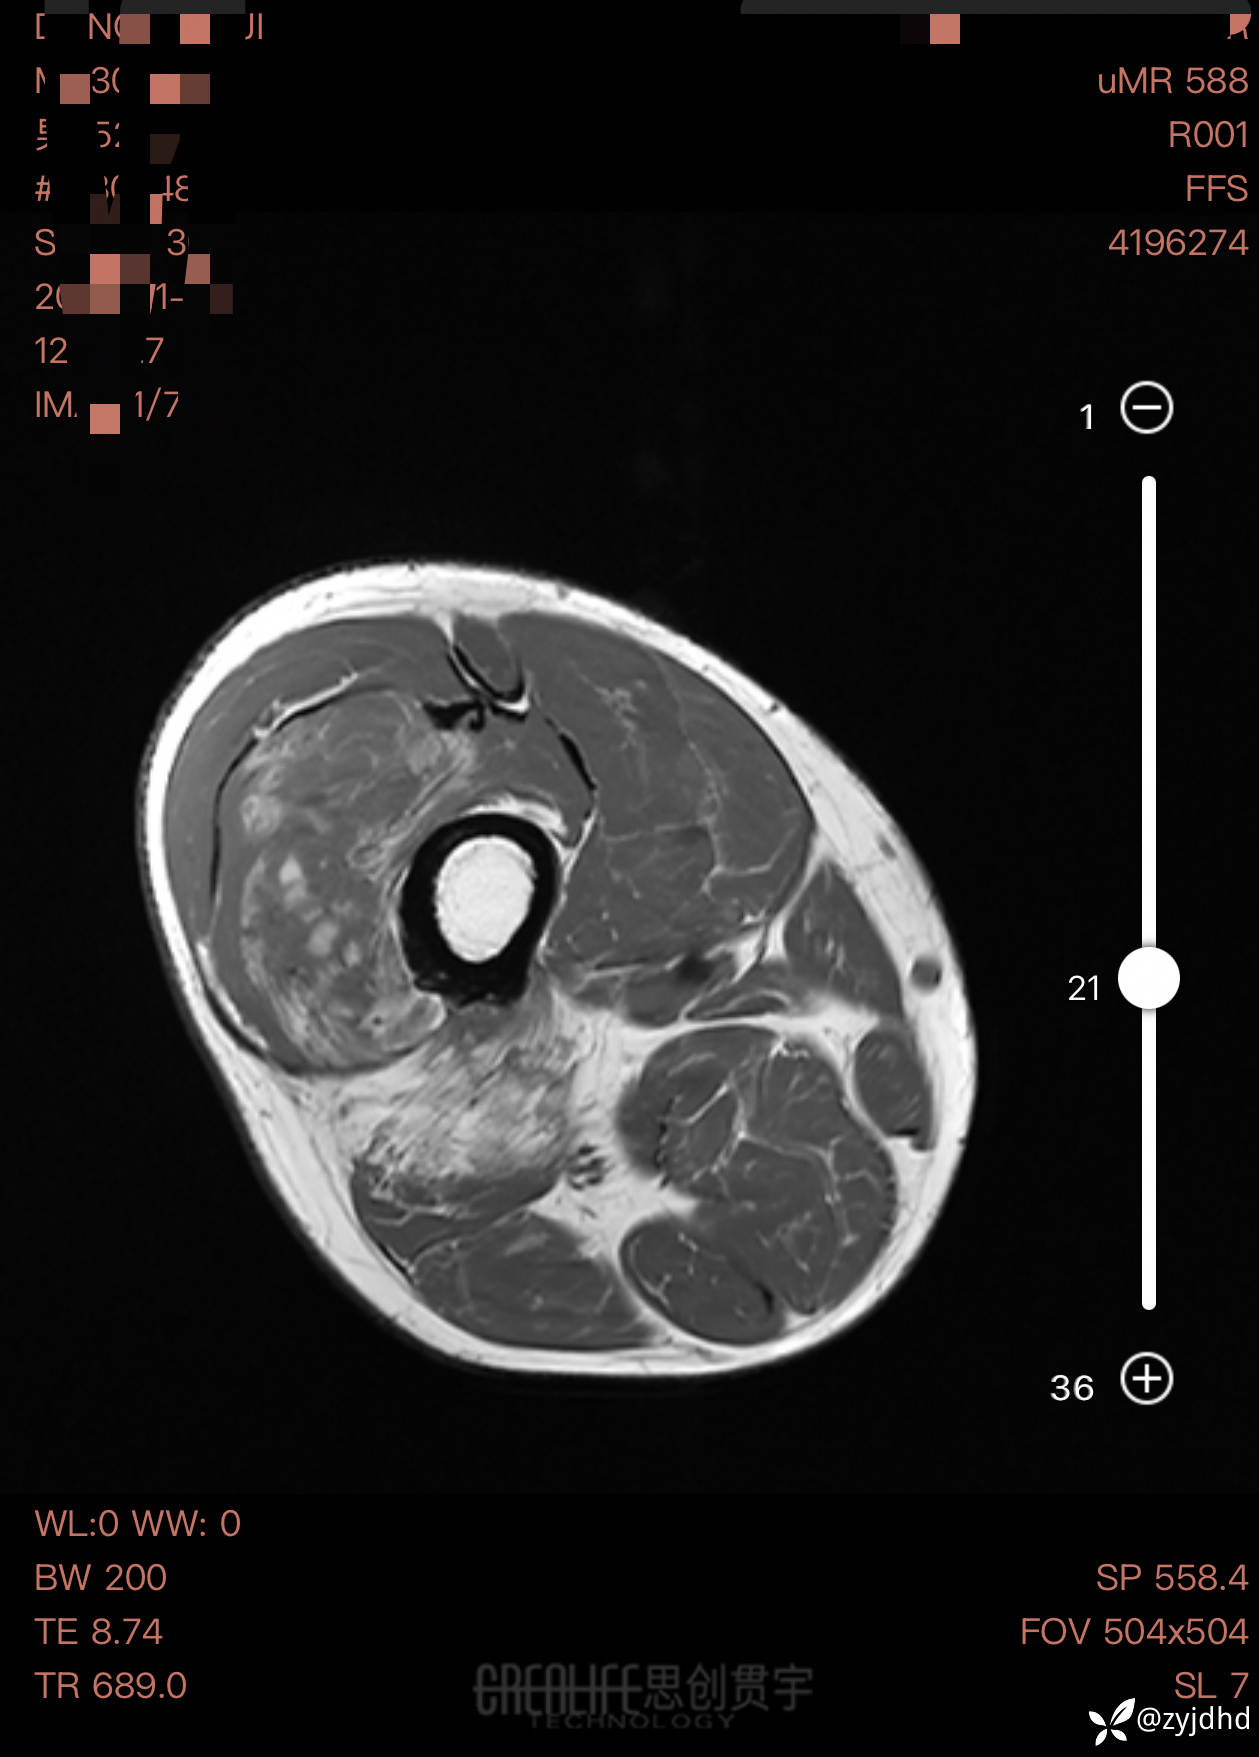

男性,发现右大腿肿物20年。